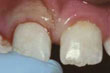

![]() | 門牙碎裂 |